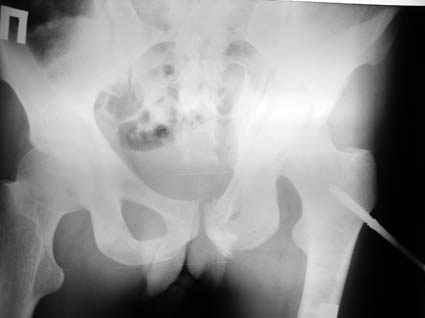

Re: Повреждение вертлужной впадины 2,5 мес.

Это обзорные и косые снимки